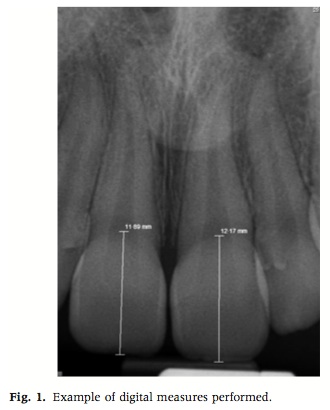

這個研究室使用數位的x-rays, 去調出五個不同世代的患者資料:10,25,40,55,70 (+-3). 然後去計算上下顎正中門齒的長度.

結果70歲的那一組跟10歲的那一組, 平均來說上顎正中門齒短了1.01mm, 下顎正中門齒短了1.46mm. 在治療上可供參考.